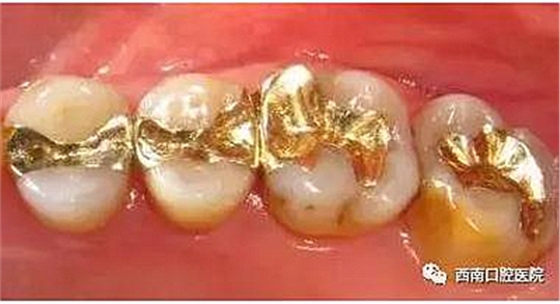

清潔干凈齲洞之后,然后醫(yī)生會用專用的充填材料進行充填,以恢復牙齒原來的形狀和大小。通常使用的充填材料有銀汞合金、復合樹脂材料、金或瓷等。

我們來看下各個材料充填之后的顏值吧!

黃金的耐磨性很高,對齲洞邊緣有很優(yōu)秀的適應性并且完全無毒,是很好的充填材料,但是黃金價格昂貴且對牙醫(yī)技術(shù)要求高。